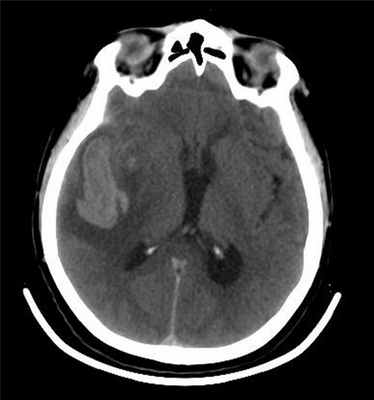

Больная Х., 66 лет, поступила в Институт нейрохирургии на 3-и сутки после интракраниального кровоизлияния из аневризмы. Оценка по шкале Ханта—Хесса — V степень. На момент поступления: уровень сознания — кома II, температура тела 38,0 °С. Дыхание аппаратное, искусственная вентиляция легких в режиме IPPV. Гемодинамика нестабильная с тенденцией к артериальной гипотензии. Артериальное давление поддерживалось внутривенным введением вазопрессоров на уровне 120—140/79—85 мм рт.ст. Компьютерная томография головного мозга обнаружила внутримозговую гематому в височной доле справа с субарахноидальным распространением крови и отеком мозга (рис. 1).

Рисунок 1. Компьютерная томограмма при поступлении: определяется внутримозговая гематома правой височной доли. По данным церебральной ангиографии в области бифуркации ВСА была обнаружена артериальная мешотчатая аневризма размером 4,2×3,7 мм. Учитывая тяжесть состояния, больной был установлен вентрикулярный дренаж с датчиком внутричерепного давления (ВЧД), которое на тот момент составляло 30—32 мм рт.ст.